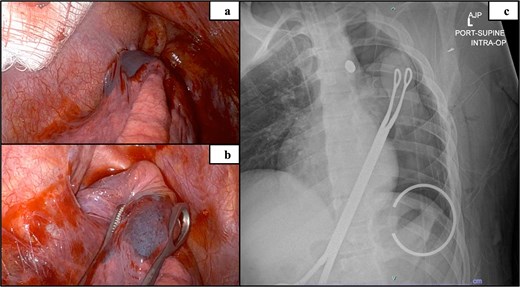

Three 8 mm robotic ports were placed: #1 in the 5th intercostal space anterior to the GelPoint, #2 in the 5th intercostal space/midaxillary line, and #3 in the third intercostal space/midaxillary line. The GelPoint cap was placed with a 10 mm port and insufflation was initiated at 8 mmHg. At this time, 100 ml of bright clotted blood was visualized in the inferoposterior mediastinum. It was unclear if this blood originated from the lung or mediastinum but was not associated with trochar placement and did not reaccumulate. The GelPoint cap was removed and insufflation was discontinued for placement of a sponge stick for manipulation of the lung and for compression of any active bleeding. The lung was carefully peeled off the superior mediastinum without hemorrhage and was inspected. Port #3 was removed and the incision was widened to allow for finger placement and manual palpation of the lung, which indicated no bullet trapped in the lung tissue. Intraoperative radiography confirmed that the bullet was still in the mediastinum (Fig. 3b). The surgical team then deemed it to be safe to proceed with robotic VATS.

Intraoperative mediastinum adhesion visualized via robot (a), isolated upper lobe suspicious of containing bullet remnant (b) and intraoperative radiograph confirming bullet localized in the mediastinum (c).